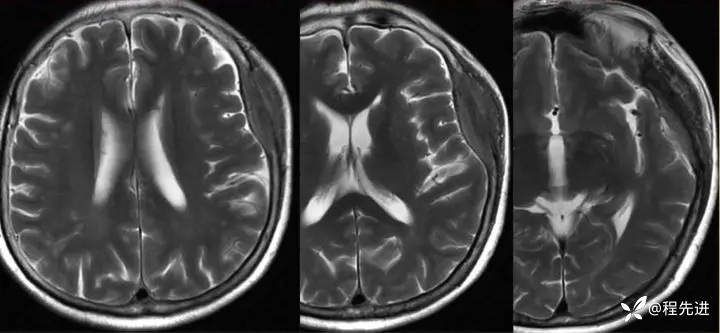

【患者信息】:女,58岁

【现病史及既往史】:发现头皮肿块,进行性增大2年余

影像检查:

2年后: